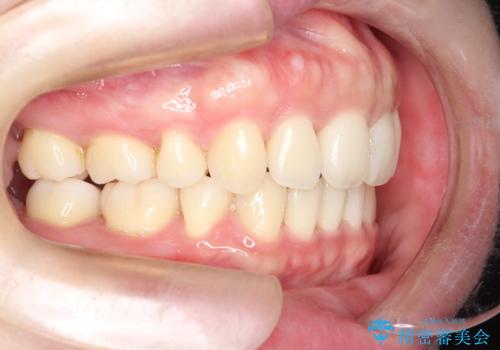

【審美装置】癒合歯がある方の治療

- 前歯の前突を主訴に来院されました。

下の前歯は癒合歯がある珍しいケースです。

治療に関しては小臼歯を4本抜歯して前歯を下げるような計画を立てて治療しました。